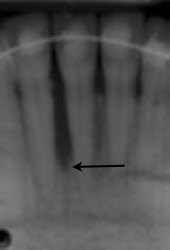

Periodontal Regeneration Case Studies Performed by Dr. Orth

Case 1: Before and after Periodontal Regeneration